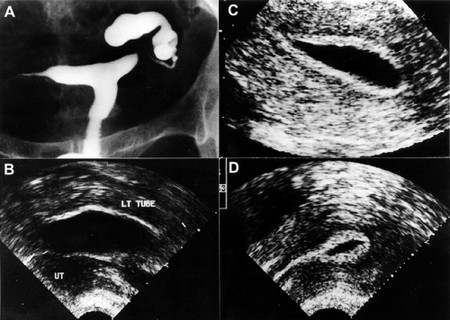

步驟7:查查“管道”。

檢查輸卵管是否通暢,可以使用輸卵管通液、子宮輸卵管造影、宮腔鏡下輸卵管通液等。這些檢查應(yīng)該在月經(jīng)結(jié)束后的3~7天內(nèi)進(jìn)行,并且應(yīng)該遵循簡單先于復(fù)雜,非侵入性先于侵入性的原則。